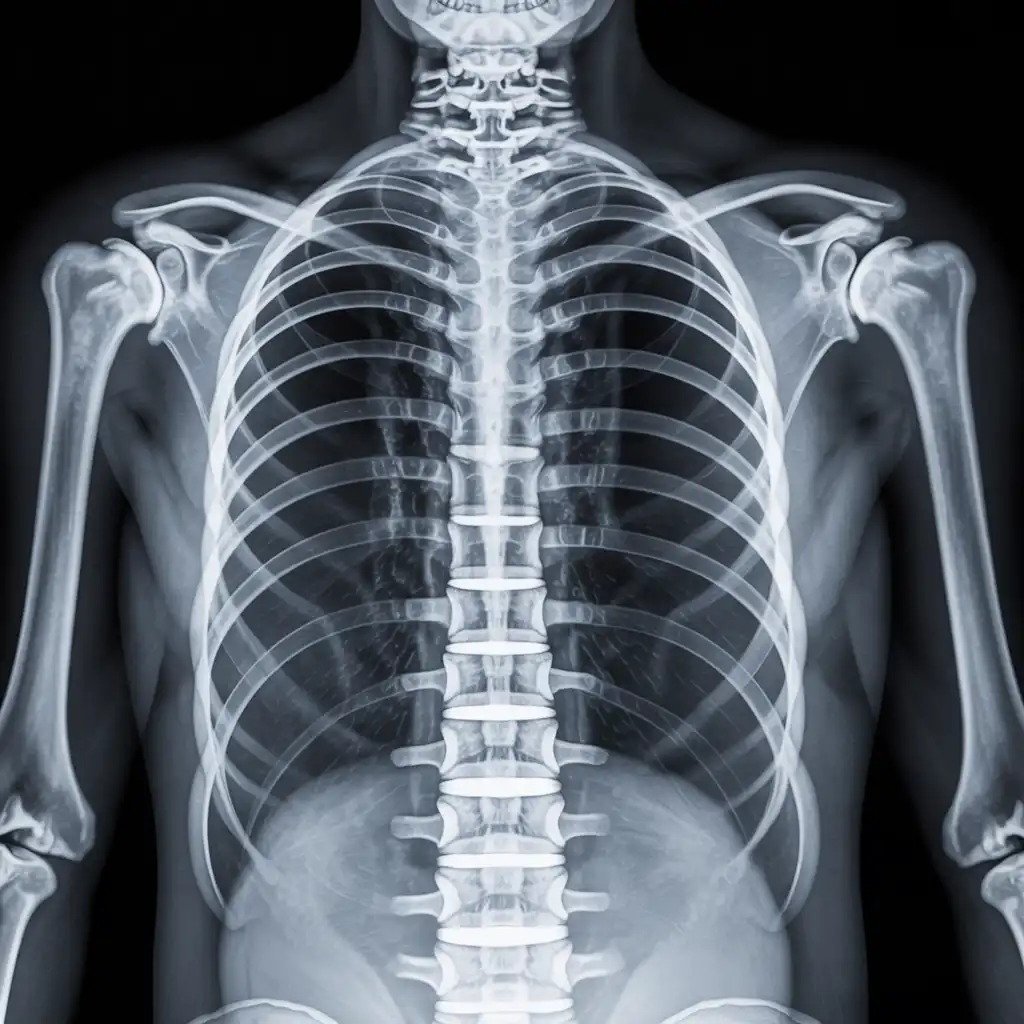

Siamo un gruppo di tecnici di radiologia abilitati, con una lunga esperienza maturata in reparti ospedalieri e strutture diagnostiche del territorio. Abbiamo scelto di portare la nostra competenza direttamente nelle case dei pazienti, offrendo esami radiologici a domicilio con standard elevati di qualità e sicurezza.

Nel corso degli anni abbiamo effettuato migliaia di radiografie a domicilio in abitazioni private, RSA, centri di assistenza e strutture per anziani, utilizzando apparecchi digitali portatili certificati che garantiscono immagini precise e tempi di esecuzione rapidi.

Con Radidom Salerno poniamo la persona al centro: attenzione, professionalità e tecnologia avanzata per offrire un percorso diagnostico comodo, umano e totalmente accessibile anche a chi ha difficoltà negli spostamenti.